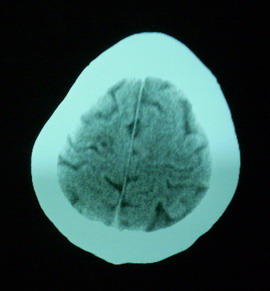

男,70岁,左侧肢体活动障碍口角向右侧歪斜2天,有高bp病史

pe:神情,能与之正常交流,吐字不清,180/90mmhg,双瞳孔无异常,左侧肢体肌力1级 b(+)

1、右侧基底区及外囊区腔隙性脑梗塞。2、脑萎缩。

右基底节内囊前支区腔隙性脑梗塞,脑萎缩

右基底节区脑强隙 右基底节区低密度影密度太低 边界清 不会是2天的梗赛灶

2天左右的腔隙性脑梗死ct多难以发现 何况你的机器又差 很难显示 即使显示密度应该略低影

边缘模糊

支持腔梗。左内囊后肢亦有病灶